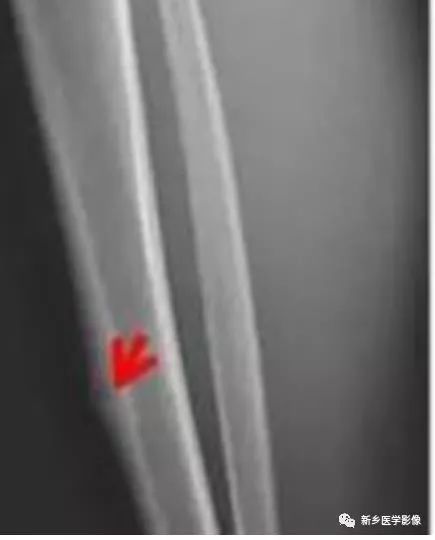

—皮质的疲劳骨折:

也可出现明显的骨质增生硬化,但其中央为骨折线,而非圆形的瘤巢影

平片仍然是诊断骨样骨瘤的重要手段;